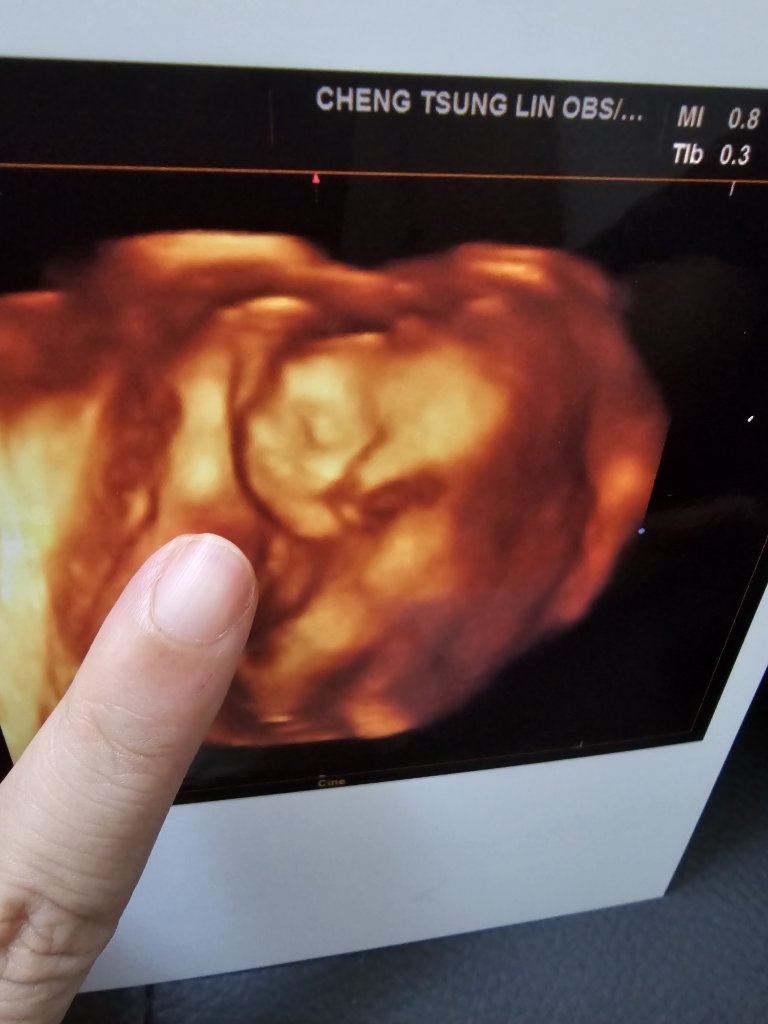

產檢報告

魚卵孵化日記

終於拍到臉了~~~~

之前魚卵都用手死死摀著臉,不給拍,這次好不容易終於拍到長相了

其實這次照超音波一開始也看不到臉,也是摀住,就連醫生都說他好像很害羞XDDDDDD

最後是醫生一直搖我肚子+喬角度才終於拍到這張側臉

不過我真的是菜鳥媽媽,彩色超音波照真的是有看沒懂,是醫生教我怎麼看才看得出所以然

我二妹就不愧是這方面的學姊,她一看到照片就能清楚地描述這是寶寶側臉照,還說魚卵鼻子很挺 (我:?????你們怎麼看出來的?)